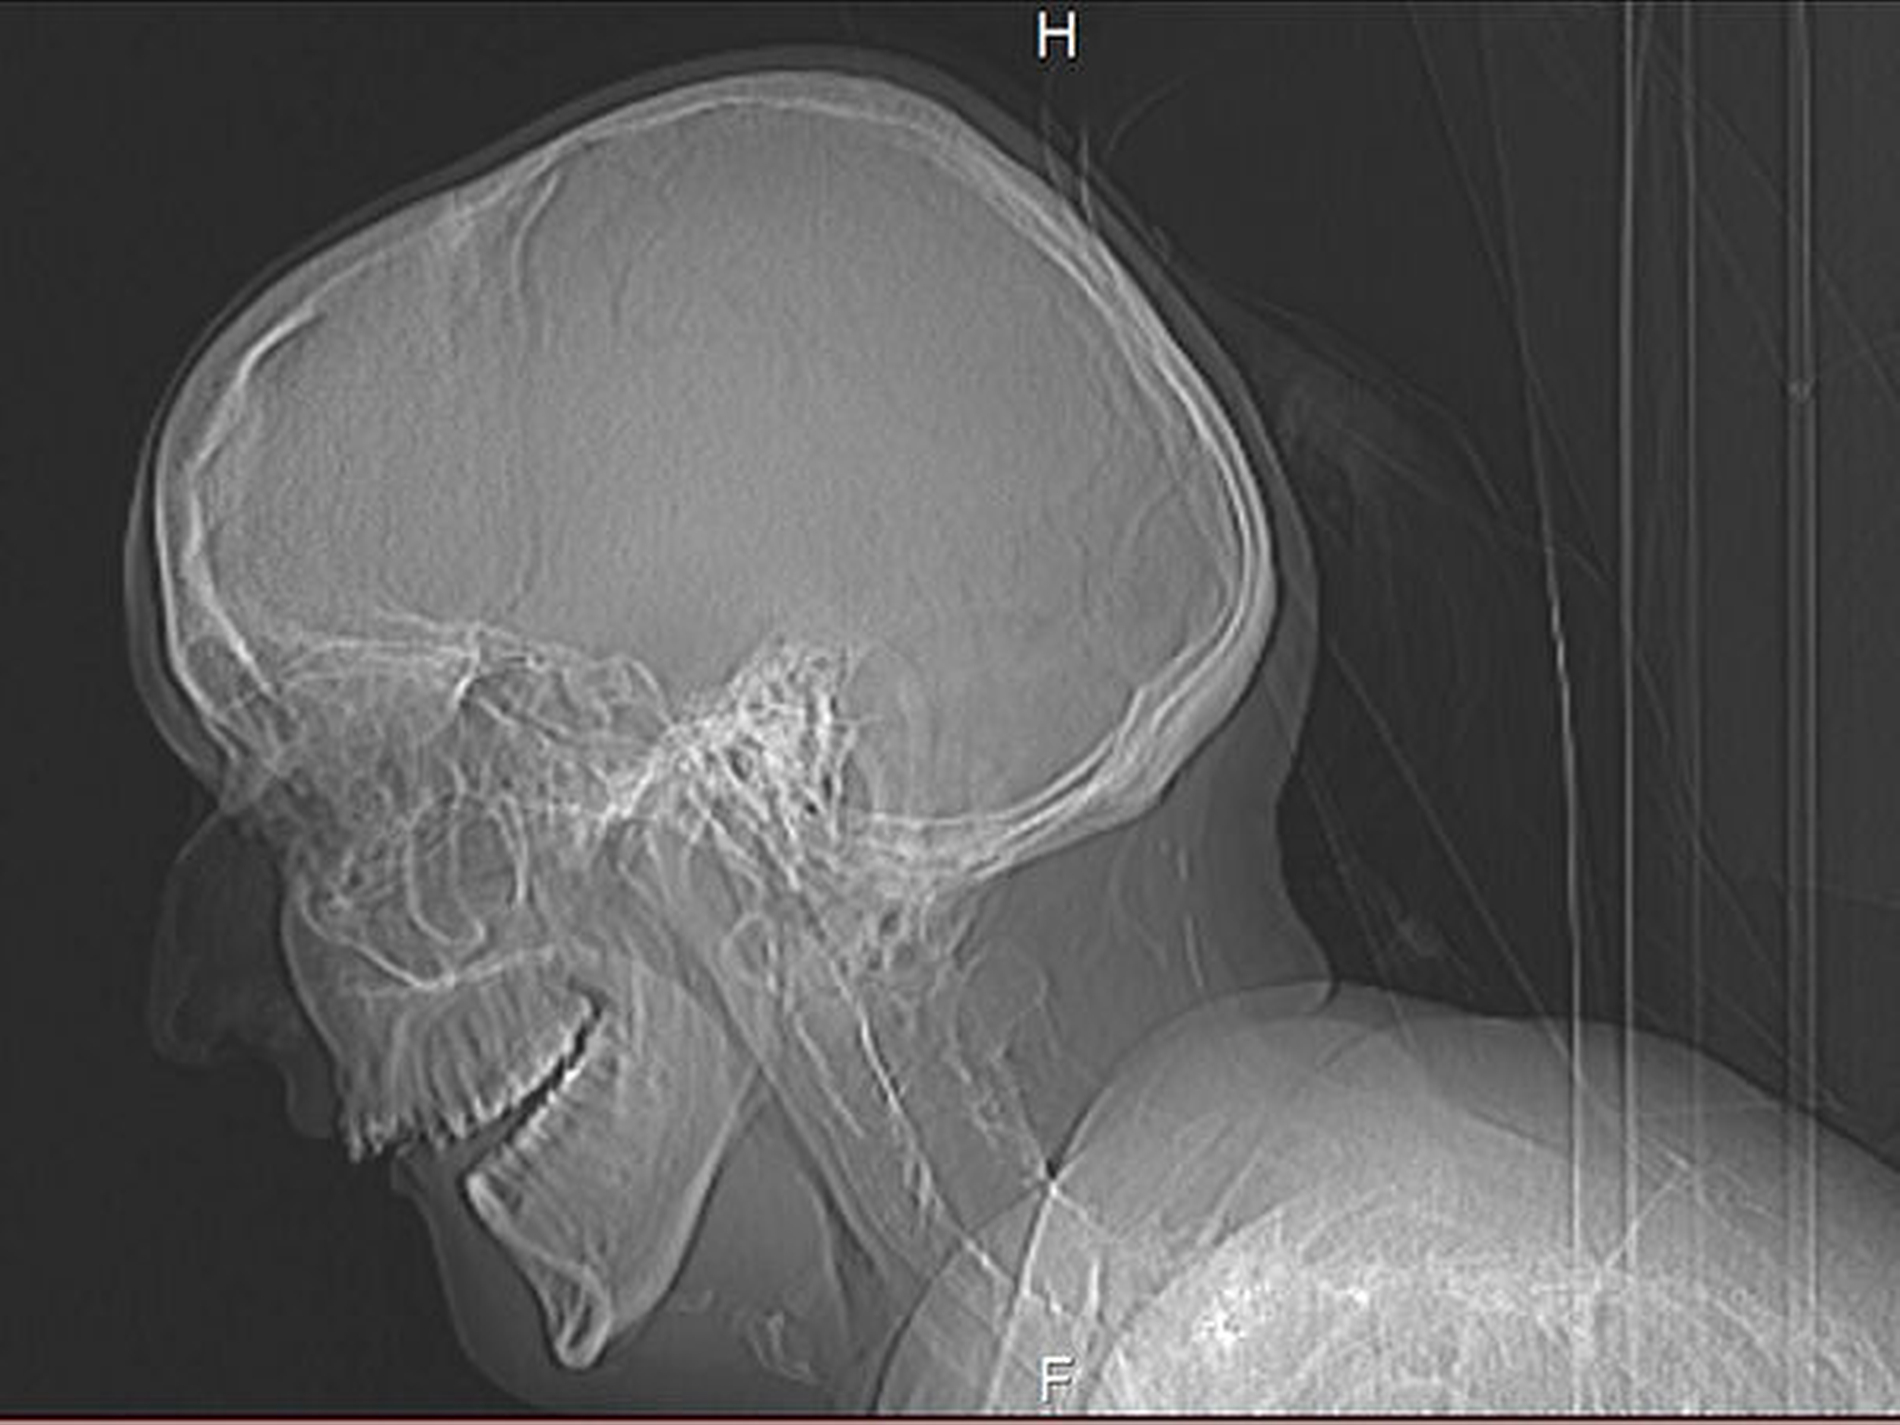

Die radiologische Diagnostik wird mit den üblichen Standardverfahren durchgeführt, sofern die Konzeptionierung des Aufnahmegerätes den körperlichen Veränderungen bei diesen Patienten gerecht wird. Im vorliegenden Fall war die Anfertigung einer Panoramaschichtaufnahme aufgrund der ausgeprägten motorischen Einschränkungen der Patientin nicht möglich. Aus dieser eingeschränkten Mobilität ergab sich die rechtfertigende Indikation für eine CT-Untersuchung, weil das Design des CT-Gerätes eine Aufnahme zum Ausschluss enossaler pathologischer Veränderungen zuließ. Die Versteifung der betroffenen Patienten kann allerdings auch dazu führen, dass nur von der Norm abweichende, unter Umständen gekrümmte Positionen eingenommen werden können. Die Frage nach dem Ausmaß der ossären Transformation von weichgeweblichen Strukturen mithilfe einer MRT-Untersuchung kann derzeit nicht beantwortet werden, weil auch in offenen Geräten eine Positionierung der Patientin nicht möglich ist.